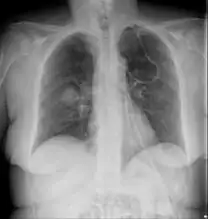

Imaging is often performed, such as CT scan of lungs and sinuses.[38] Signs on chest CT scans, such as nodules, cavities, halo signs, pleural effusion and wedge-shaped shadows, showing invasion of blood vessels may suggest a fungal infection, but does not confirm mucormycosis.[16] A reverse halo sign in a person with a blood cancer and low neutrophil count, is highly suggestive of mucormycosis.[16] CT scan images of mucormycosis can be useful to distinguish mucormycosis of the orbit and cellulitis of the orbit, but imaging may look identical to those of aspergillosis.[16] MRI may also be useful.[39]